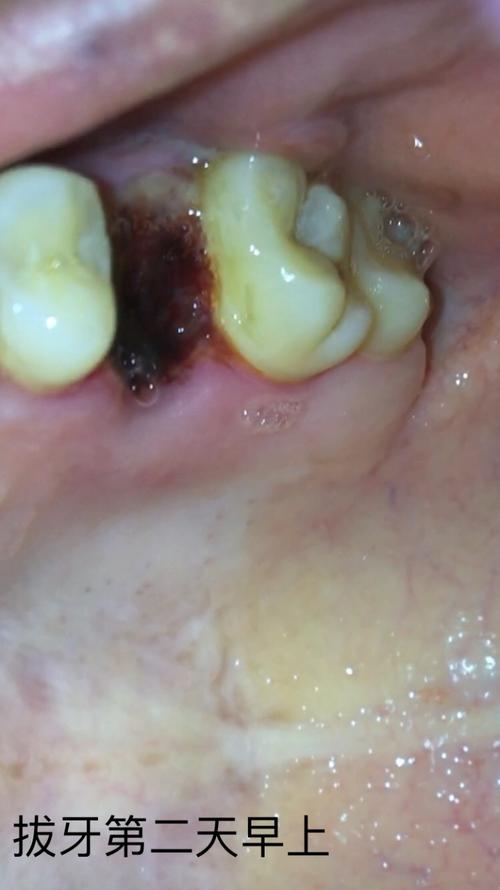

拔牙后假膜图片,拔牙后白色假膜图片

原来拔牙之后伤口会长假膜~惊了 想知道医生要如何拆线

拔牙全程(多图慎点!)恢复期全过程